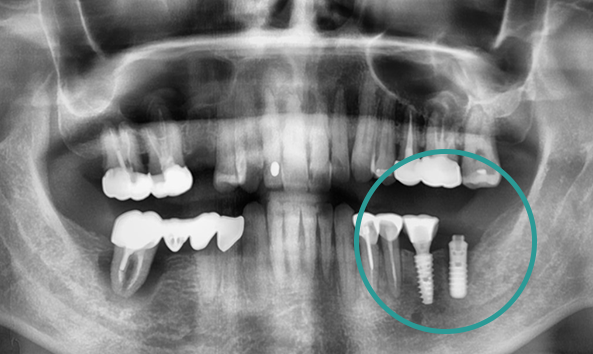

여러 원인으로 발생되는

임플란트 재수술

임플란트 환자 10명 중 1~2명은 재수술을 경험합니다.

임플란트는 시술 후 문제가 없다면

오래 사용할 수 있지만, 염증이나 부작용 등 다양한 요인으로 인해

재수술이 필요할 수 있습니다.

올디플란트치과는 정밀한 분석을 통해

근본적인 원인을 파악하고, 기존 임플란트를 살리거나 필요한 경우

재수술을 진행합니다.

01

문제 확인 및 검사

기존 임플란트 실패 원인을 파악하여 남아 있는 뼈 상태를 철저히 평가합니다.

02

뼈상태 평가 및 뼈이식고려

기존 임플란트 제거 후 뼈 이식을 진행하면 더욱 견고한 재수술이 가능합니다.

03

수술 및 예방관리

재수술 후 감염 가능성이 더 크기 때문에 철저한 예방관리가 이루어 집니다.